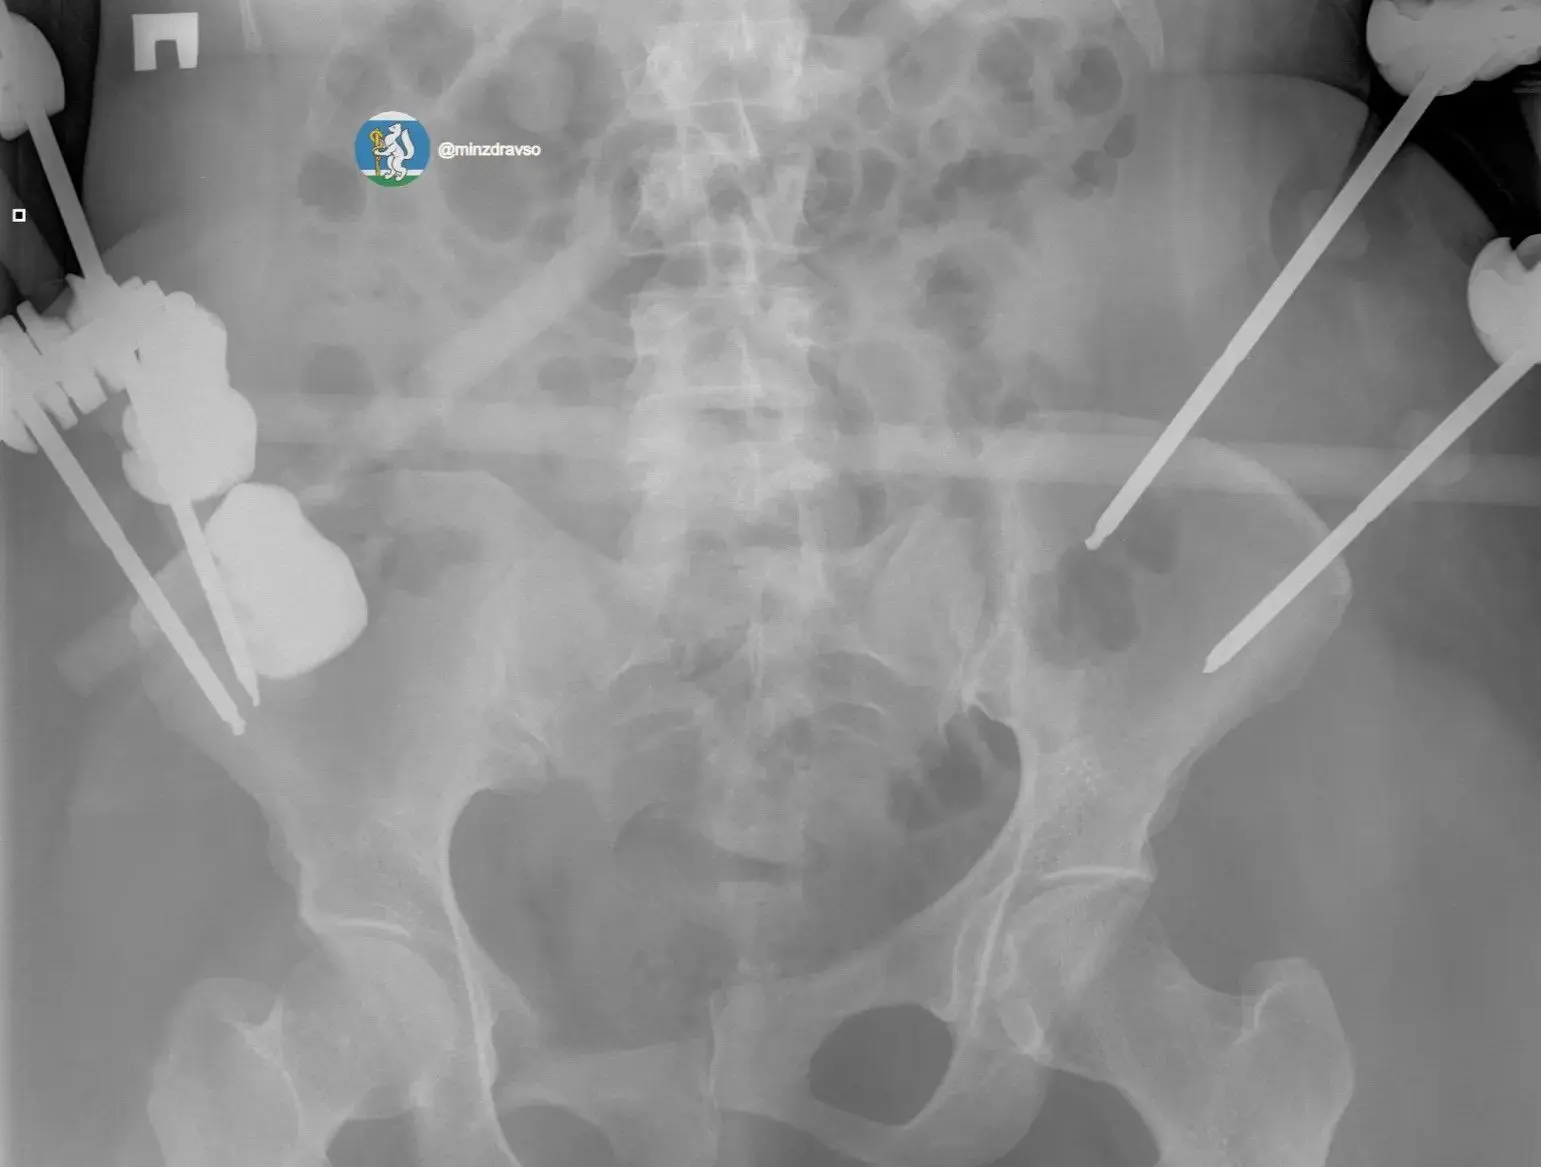

Крайне тяжелое повреждение таза представляло высокий риск массивной кровопотери, поэтому борьба за жизнь пациентки началась с немедленной стабилизации ее состояния. Медики качественгно скрепили отломки костей всех поврежденных сегментов костей и таза аппаратами внешней фиксации.